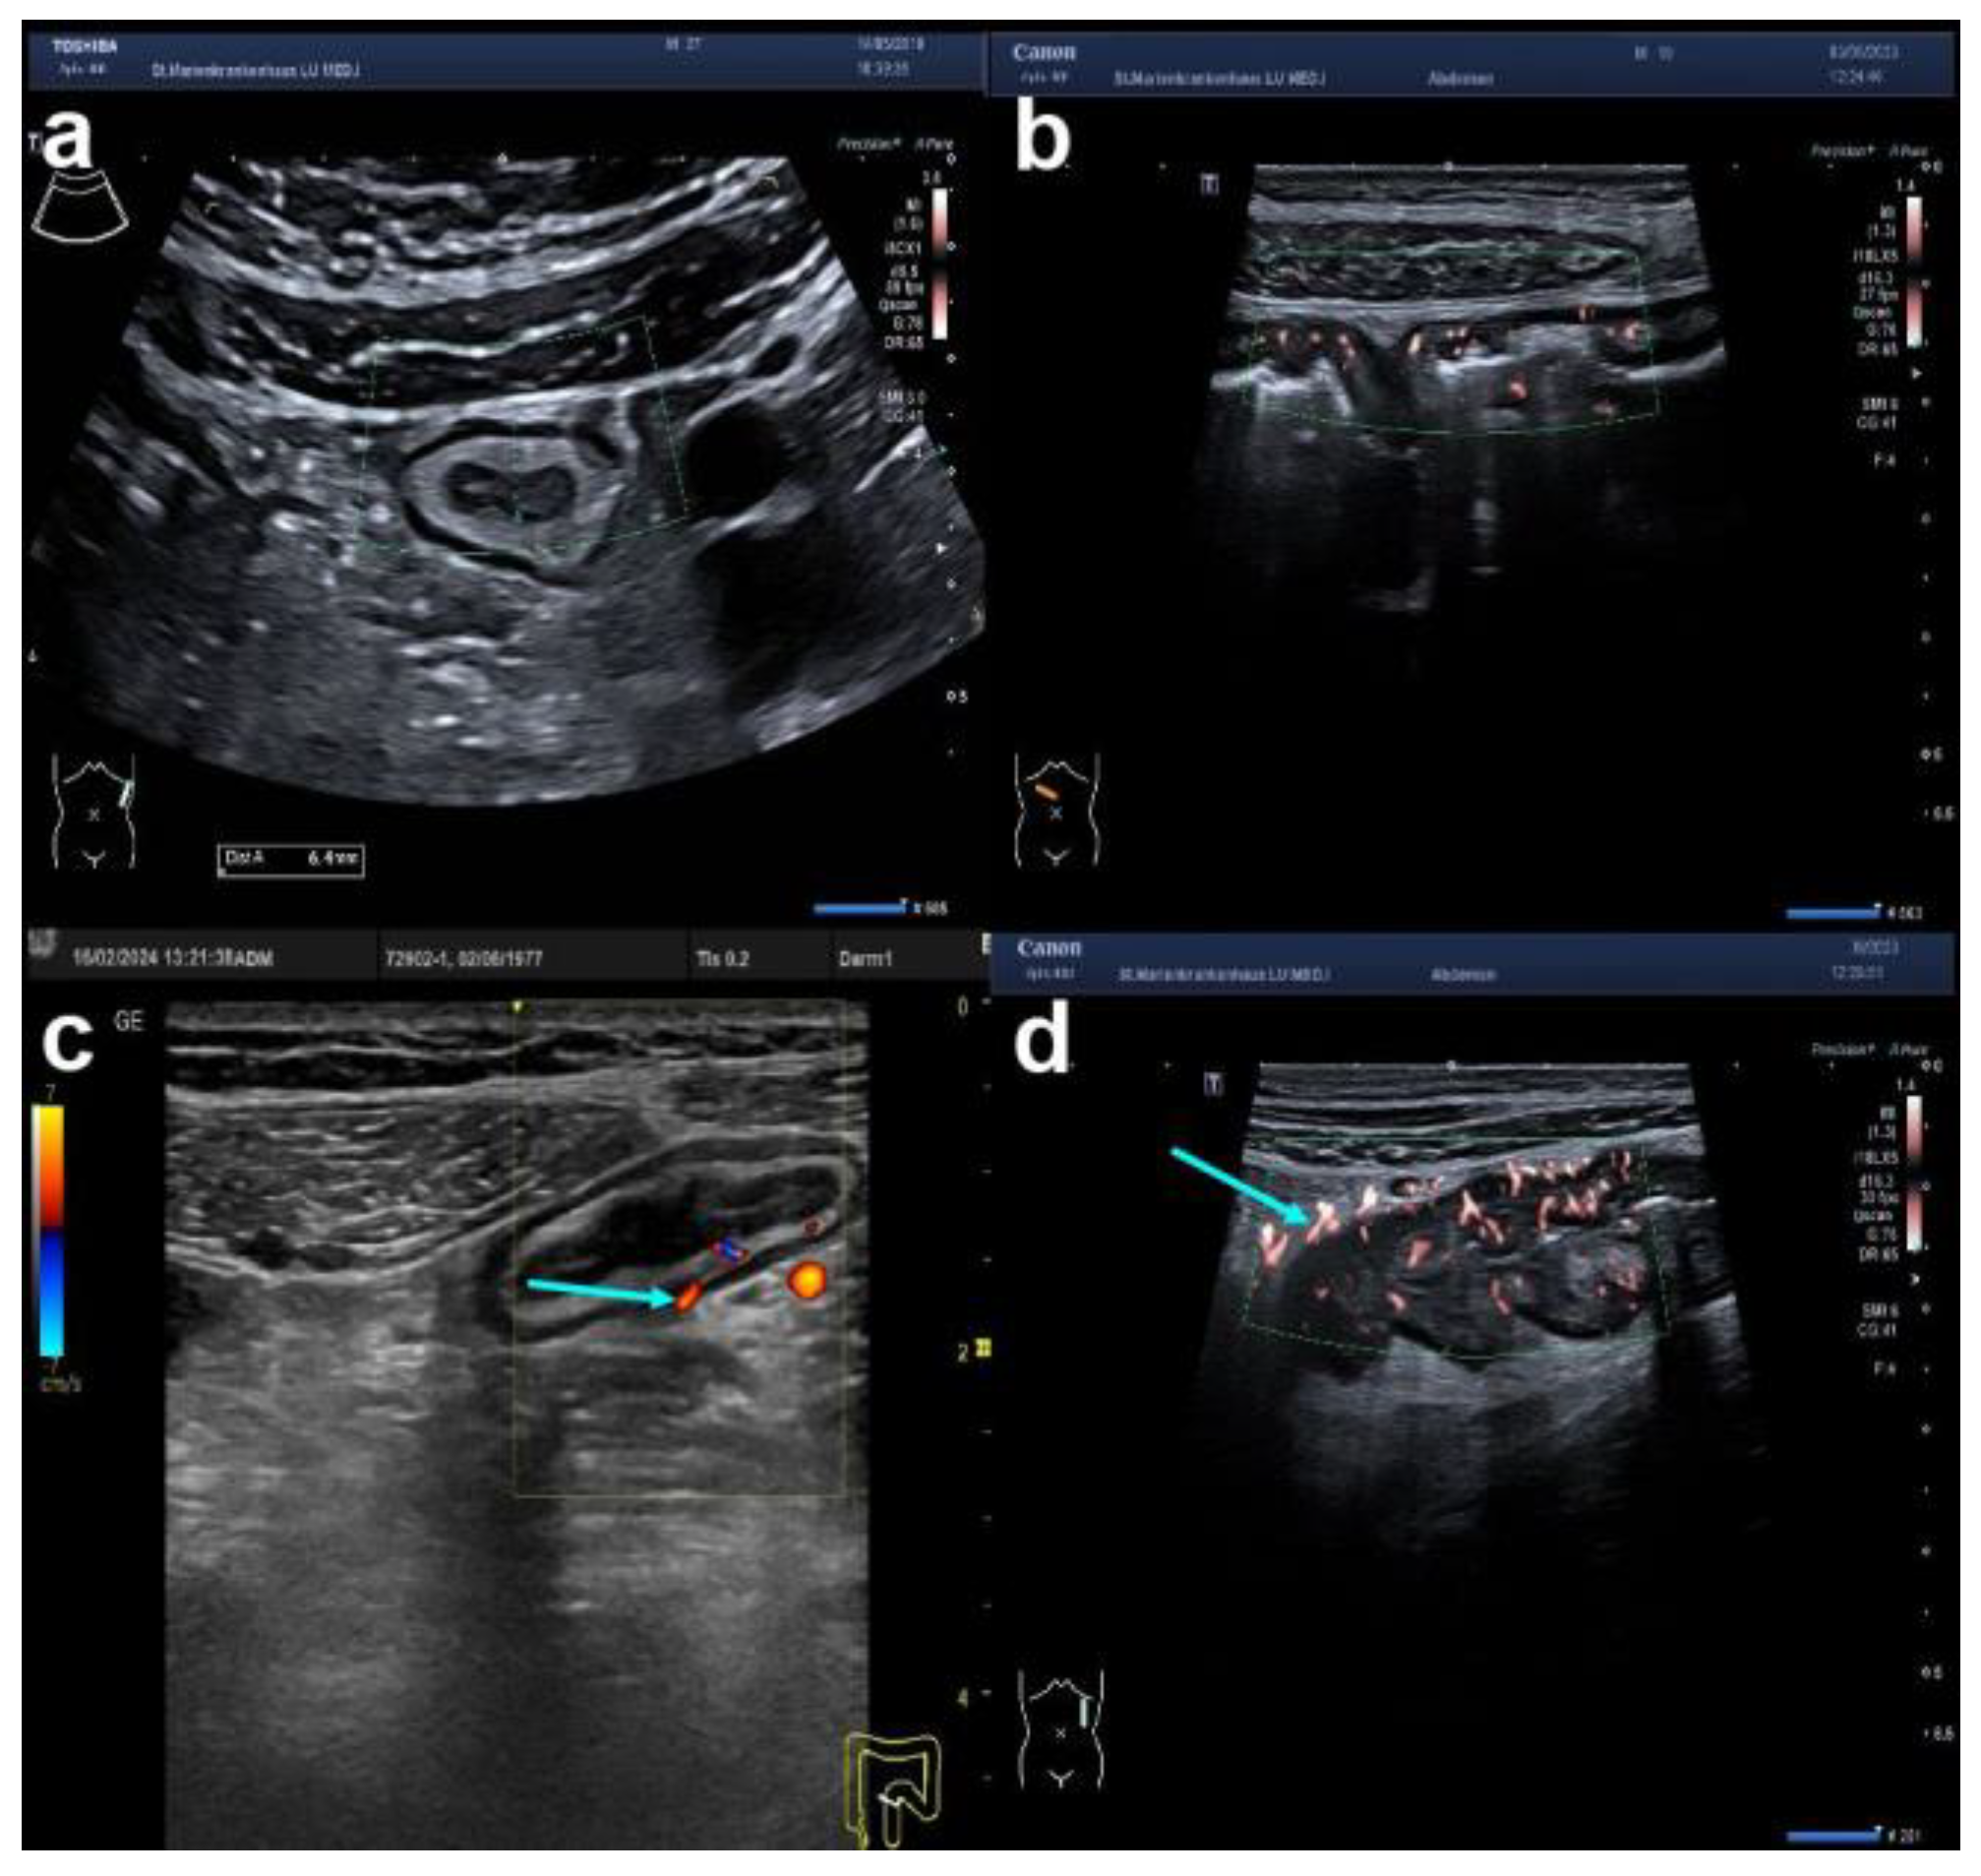

| colour Doppler signal (CDS) | vascularity | [normal; increased within the wall (dots, Limberg 2); increased within the wall (streaks, Limberg 3); increased within the wall extending into the surrounding mesentery (streaks, Limberg 4)] | |

| Surrounding | Peri-intestinal fat (creeping fat) | (inflammatory fat or iFAT) | [normal; slightly increased hyperechoic tissue; markedly increased hyperechoic tissue] |

| abscess (hypoechoic area, no CDS) | [present; absent] | ||

| fistula (hypoechoic tract) | [present; absent] | ||

| Summary: Segmental Crohn’s colitis (ascending and descending colon), maximum BWT of 11 mm, in the descending colon, loss of stratification, CDS Limberg 4 with iFAT and little ascites. | |||